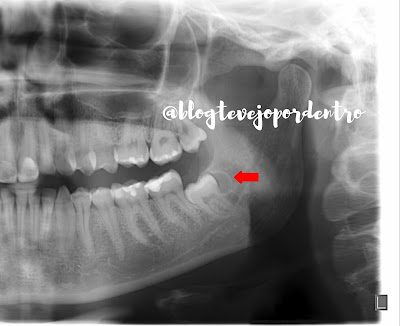

Neste recorte de radiografia panorâmica,  observamos dente 38 incluso,  mesioangulado e impactado, apresentando imagem radiolúcida,  circunscrita,  envolvendo parte da coroa ( distal) do mesmo, delimitada por halo radiopaco,  sugestiva de cisto dentígero.

Só mesmo histopatológico para confirmar.